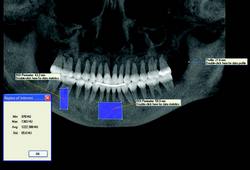

3-D software can shade images to differentiate varying densities of facial structures. Grayscale shading provides the ability to view the relationships of common internal anatomy. Traditional CT imaging renders an 8-bit grayscale (256 shades) or 12-bit grayscale (4,096 shades). Present-day scanners render images in 14-bit grayscale, providing 16,384 shades. Color coding the image by density further distinguishes anatomical structures, enabling the clinician to view pertinent anatomy while planning implant cases, such as nerves and nasal cavities, and mandibular and maxillary dimensions. Segmentation literally cuts the volume rendering, conceding top views, side views, and CT slices that produce unlimited axial, coronal and sagittal views. CBCT slices are as thin as 0.1 mm, compared to 1 mm for a conventional fan CT scan.

CBCT imaging is the ideal radiological modality for implantology due to the high quality of the produced images, software capabilities, and lower doses of radiation exposure. Two of the hottest topics regarding CBCT and implantology are virtual surgery planning and surgical guides. A virtual surgery can be performed with special software applications that enable dentists to evaluate the quality of bone through density shading and dimensions of bone can be recorded accurately with 1:1 measurement tools. It identifies common internal anatomy needed to evaluate implant placement including the jaw boundaries, adjacent teeth, nasal fossa, mandibular canal, maxillary sinus, mental foramen, and incisive canal. It also detects pathology to be avoided for implant health. Therefore, before the surgery, the clinician can confirm the appropriate implant size, location and angulation, and that plan can be fed to a 3-D printer to produce a surgical guide or stent for use during the actual surgery.